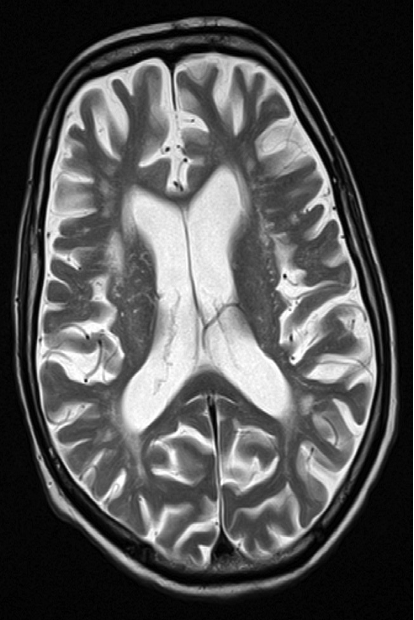

Cerebral atrophy - Axial T2-weighted MRI

showing prominence of the ventricles and generalized widening of the cerebral sulci in keeping with age-related atrophy.